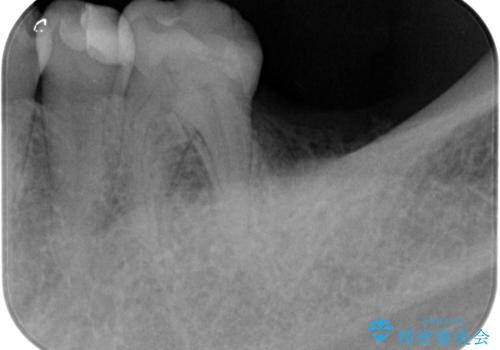

X線検査を行ったところ、セラミッククラウン下に虫歯が再発し、歯の破折も認めました。

X線を撮ることで、外から見てもわからない、歯の問題点をより正確に把握することができます。